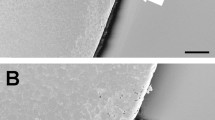

A representative low magnification image of the membrane-mounted capsule is shown with overlying sutures (n = 18) (Fig. 2A). Removable non-significant micro-tags were evident on SEM in 2/18 cases but otherwise relatively smooth edges were observed and no anterior capsule tears occurred (Fig. 2B).

Scanning electron microscopy (SEM) images of capsule edge taken at low magnification (A) ×140, ×750 and ×4000 magnification for 4, 5 and 6 mm capsulotomy (n = 18) ((B) upper to lower rows). A micro-tag is highlighted with a hatched arrow and the capsule edges at high magnifications by straight arrows.